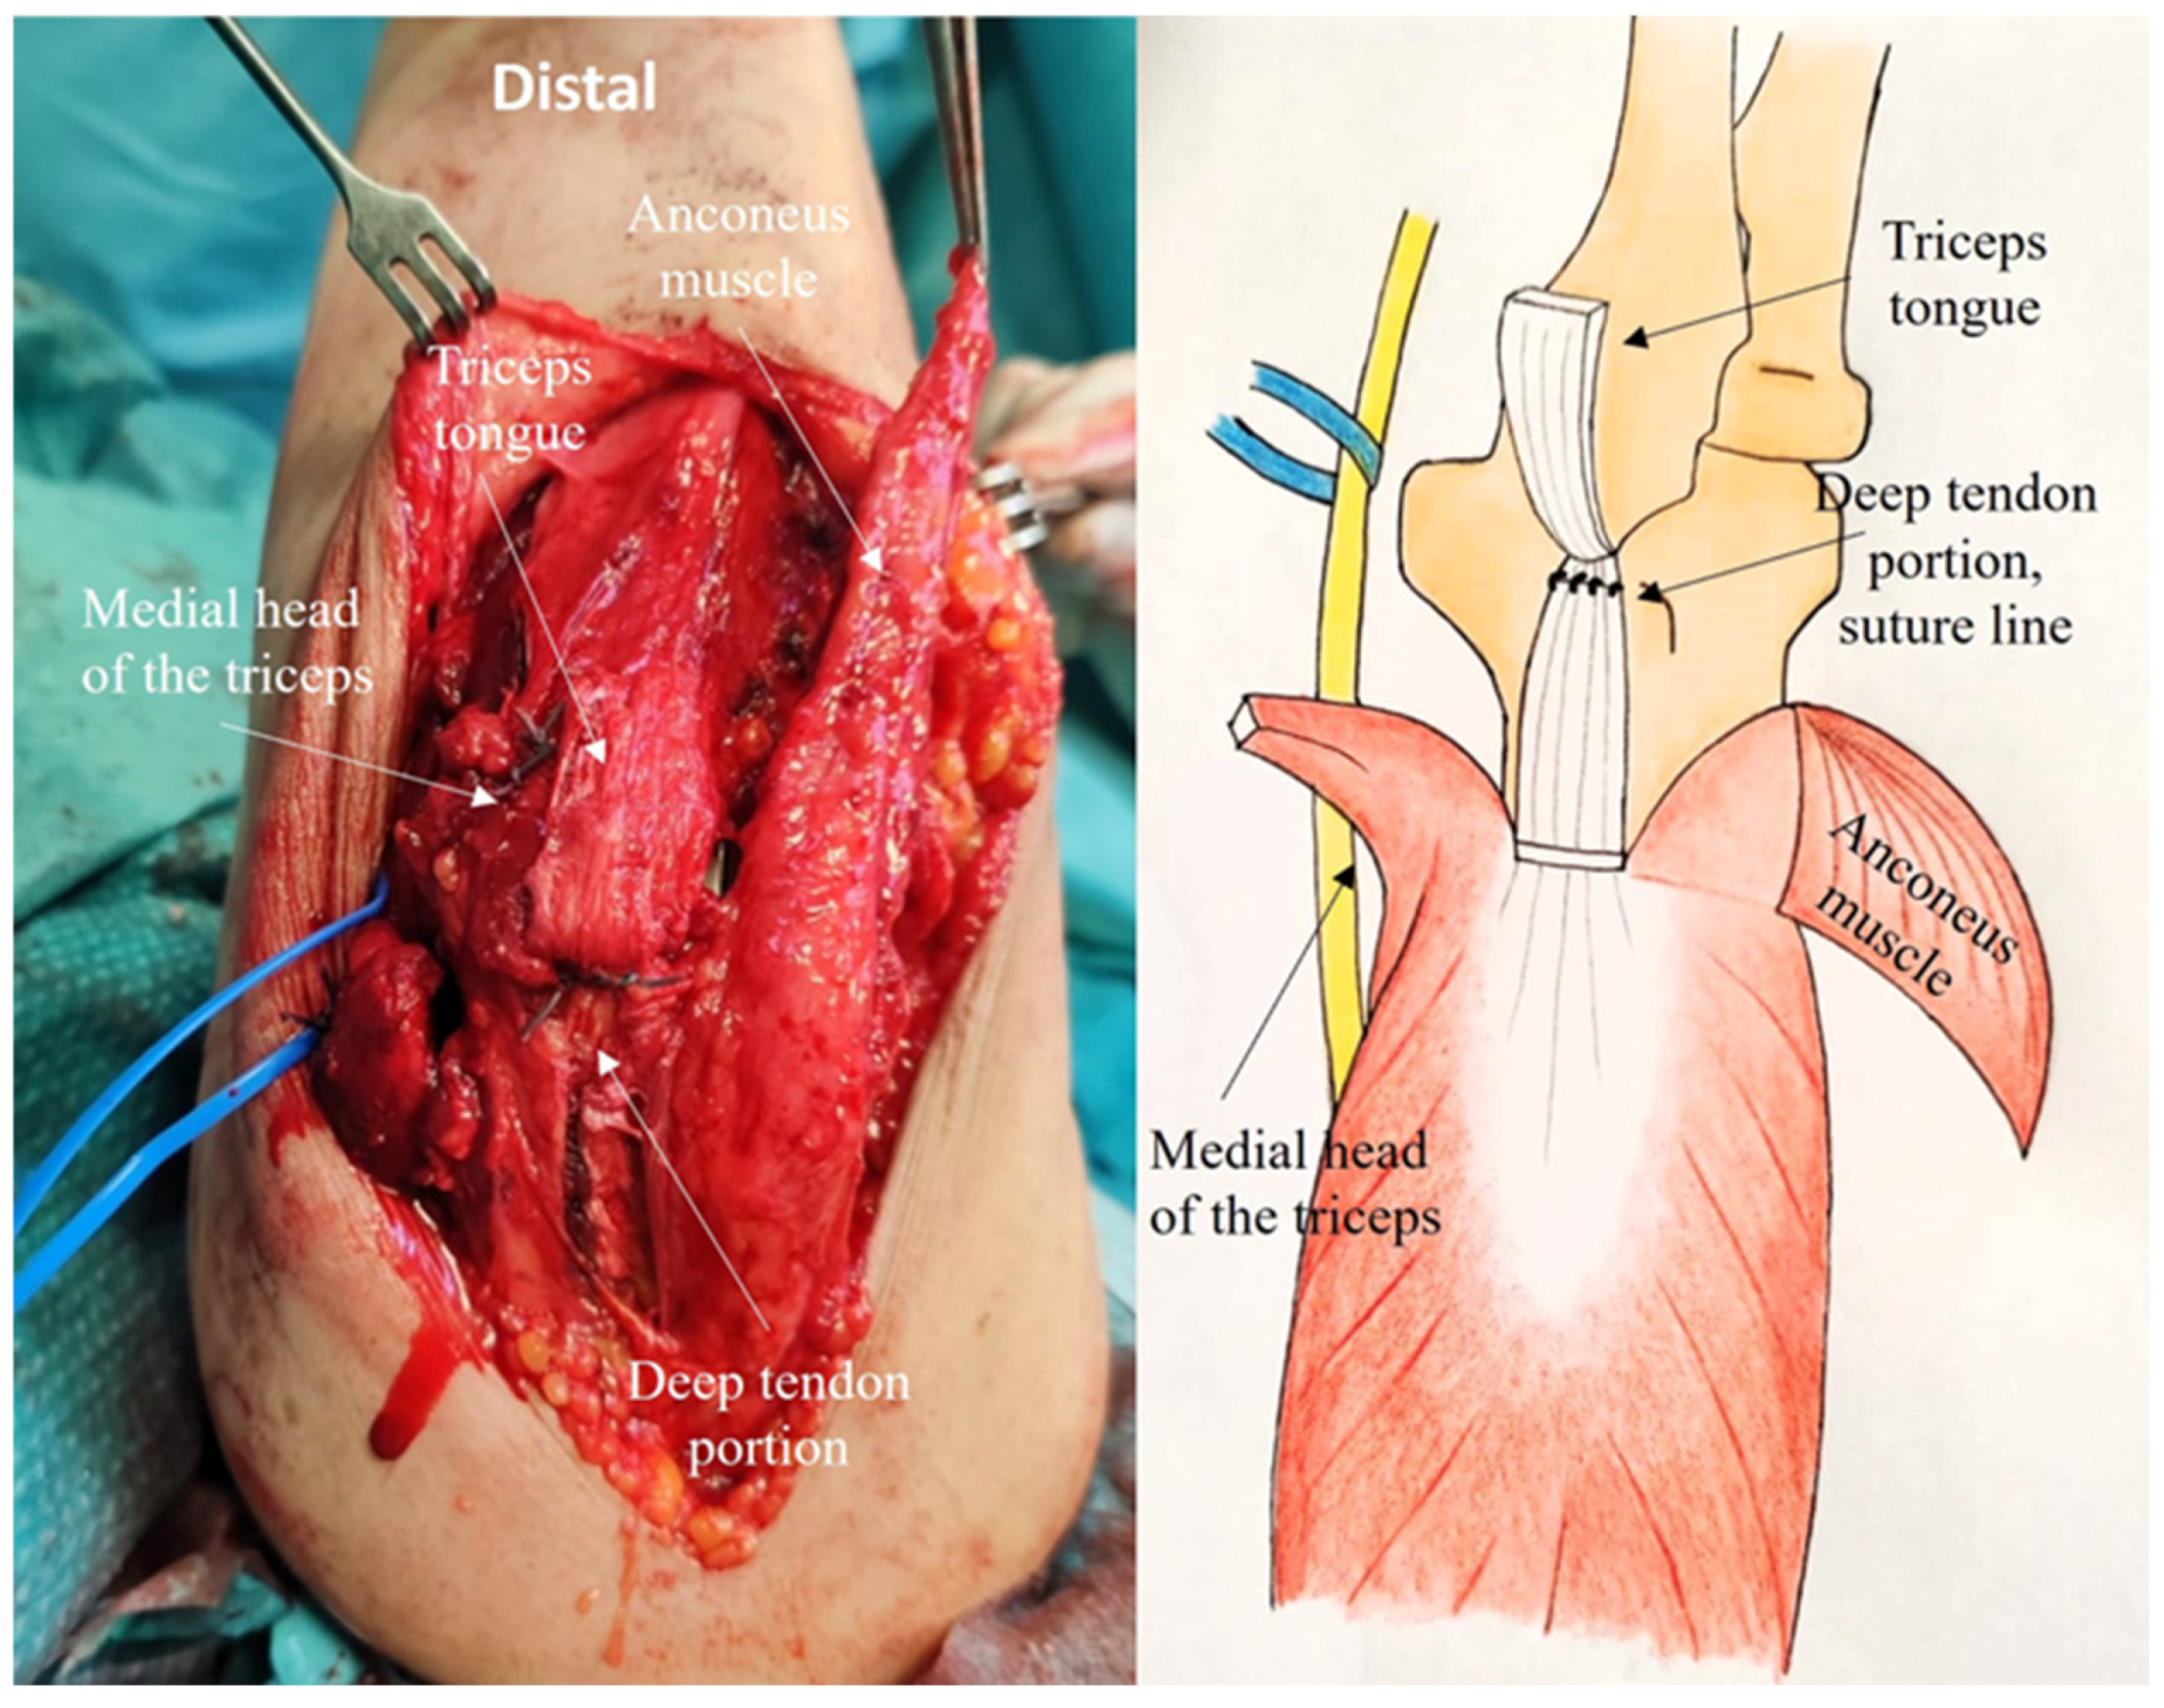

2.4. Development of the ARTT Approach